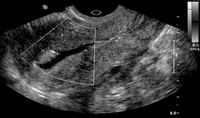

Hysterosalpingography (HSG) demonstrating bilateral hydrosalpinges

From the collection of Dr Jared C. Robins